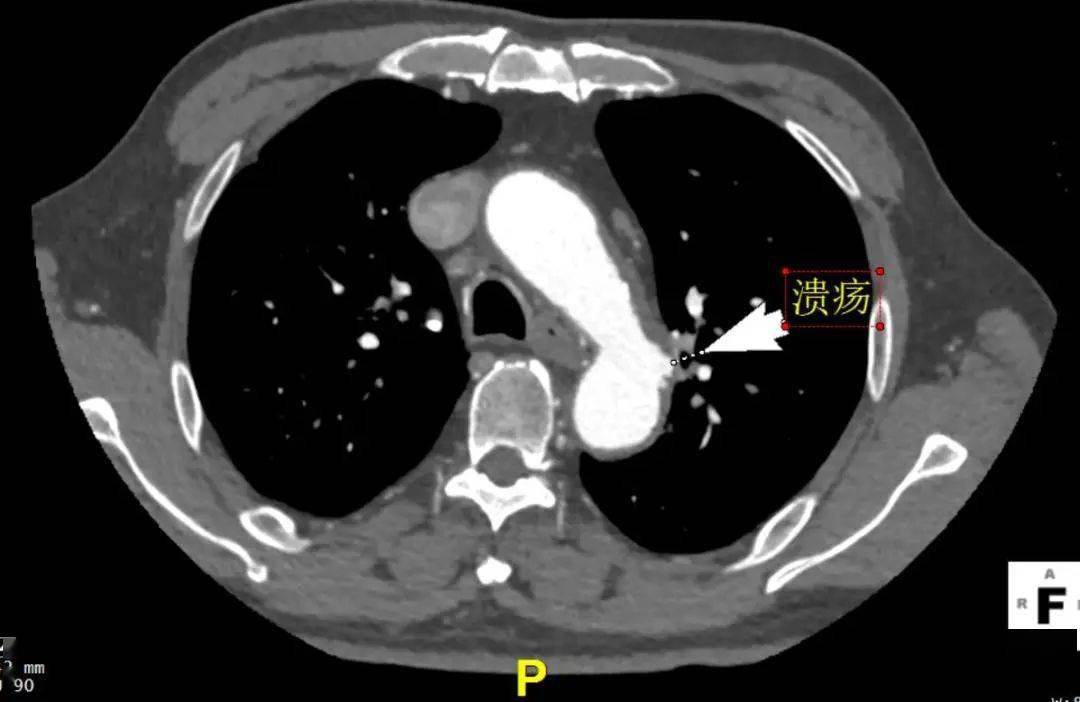

主动脉也会"溃疡"

主动脉溃疡